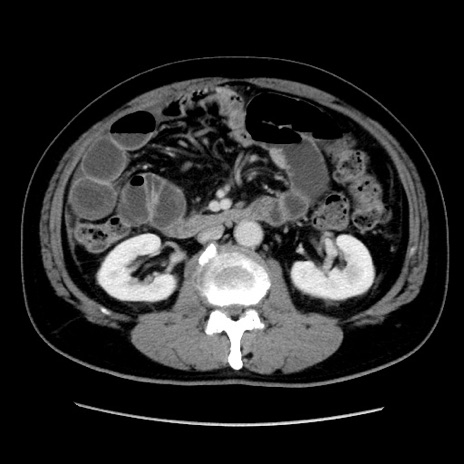

症例16(横断像)

冠状断像

【現病歴】 約1ヶ月前より間欠的に腹痛と嘔吐あり、当院消化器内科を受診したところCTで多発する肝臓のLDAを指摘され、精査中であった。以降は消化器症状は安定していたが、2日前より嘔気と腹痛があり、同日より排便・排ガスが消失した。改善認めず、 本日、救急外来を受診した。